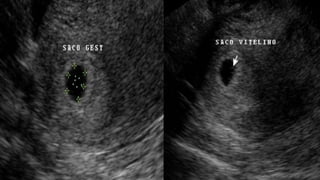

Presencia de saco gestacional:

1. Forma redondeada hasta las 7

semanas.

2 .Localizada en el fondo uterino.

3 .Anillo eco génico rodea el saco

Presencia de saco vitelino

1. Su presencia confirma la

existencia de un embrión.

2. Crece a razón de 1mm por

semana.